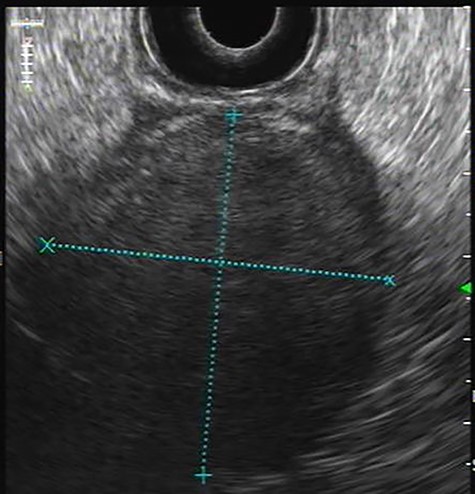

Endoscopic ultrasonography: Hypoechoic homogeneous lesion, growing on the 4th layer of gastric wall with regular contours, well-defined limits and negative Doppler sign; no cystic aspects were found; gastrointestinal stromal tumour diagnosis was suggested.

Presenting an initial clinical picture of epigastric pain and nonspecific dyspeptic symptoms, the patient underwent upper gastrointestinal endoscopy (Fig. 1) where a subepithelial lesion was found, mandating further investigation. Endoscopic ultrasonography (Fig. 2) arose suspicion of GIST and computed tomography scan (Fig. 3) revealed an exophytic lesion with 97 × 77 × 57 mm rising from the gastric greater curvature, with no signs of metastatic or locally advanced disease.